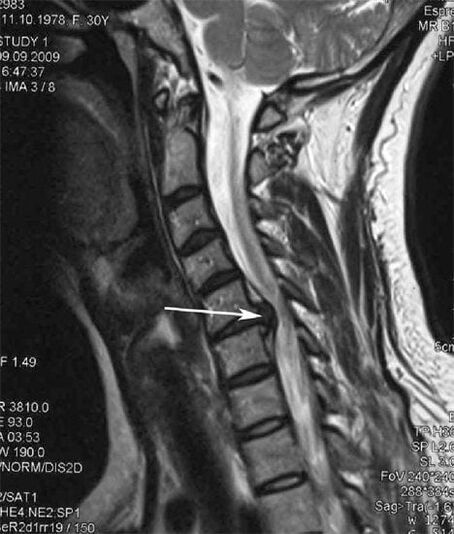

İlk aşamalarda, osteokondroz MRI kullanılarak tespit edilir. Daha sonra patoloji radyografi kullanılarak teşhis edilebilir. Servikal omurganın radyografilerinde omurlar arasındaki mesafede bir azalma, faset eklemlerdeki patolojik değişiklikler ve osteofitoz fark edilir hale gelir.

| Servikal osteokondroz | Bir veya daha fazla omurga hareket segmentinde patolojik değişikliklerin ortaya çıkması. Omurga hareketliliğinin bozulması, miyofasyal ağrı sendromlarının gelişimi ve omurilik köklerinin sıkışması | Başın arkasına ve üst ekstremitelere yayılan, servikal bölgede ağrı, parestezi ve motor bozukluklar. MR ve radyografilerde omurgadaki karakteristik değişikliklerin tespiti (osteofit, omurlar arasındaki mesafenin azalması, omurlararası eklemlerde hasar belirtileri) |

Birçok kişi aniden ağır bir şey kaldırıldığında ortaya çıkan şiddetli ağrı nedeniyle boynunu çeviremediğinden şikayetçidir. Bu fenomen fıtıklaşmış bir diskin oluşumunu gösterir. Sırt, boyun ve üst ekstremitedeki ağrıların nedeni omurilikten çıkan sinir köklerinden birinin sıkışmasıdır.